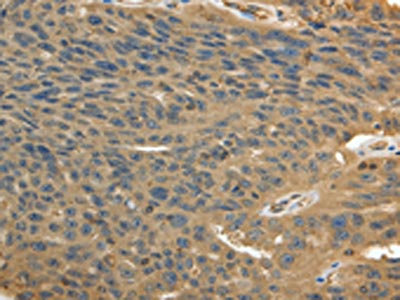

The image on the left is immunohistochemistry of paraffin-embedded Human breast cancer tissue using CSB-PA187078(MSN Antibody) at dilution 1/30, on the right is treated with fusion protein. (Original magnification: ×200)